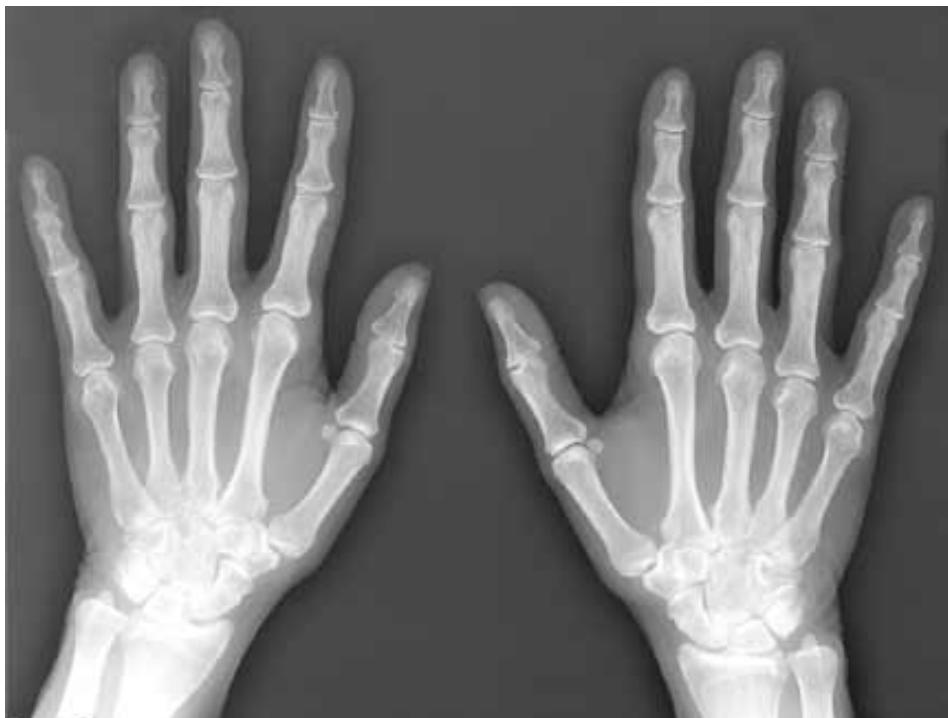

- Hand Joints (Below 18 years):

- Distal ends of metacarpals not united with shafts

- Proximal ends of phalanges not united

- Above 18: All hand bones united (